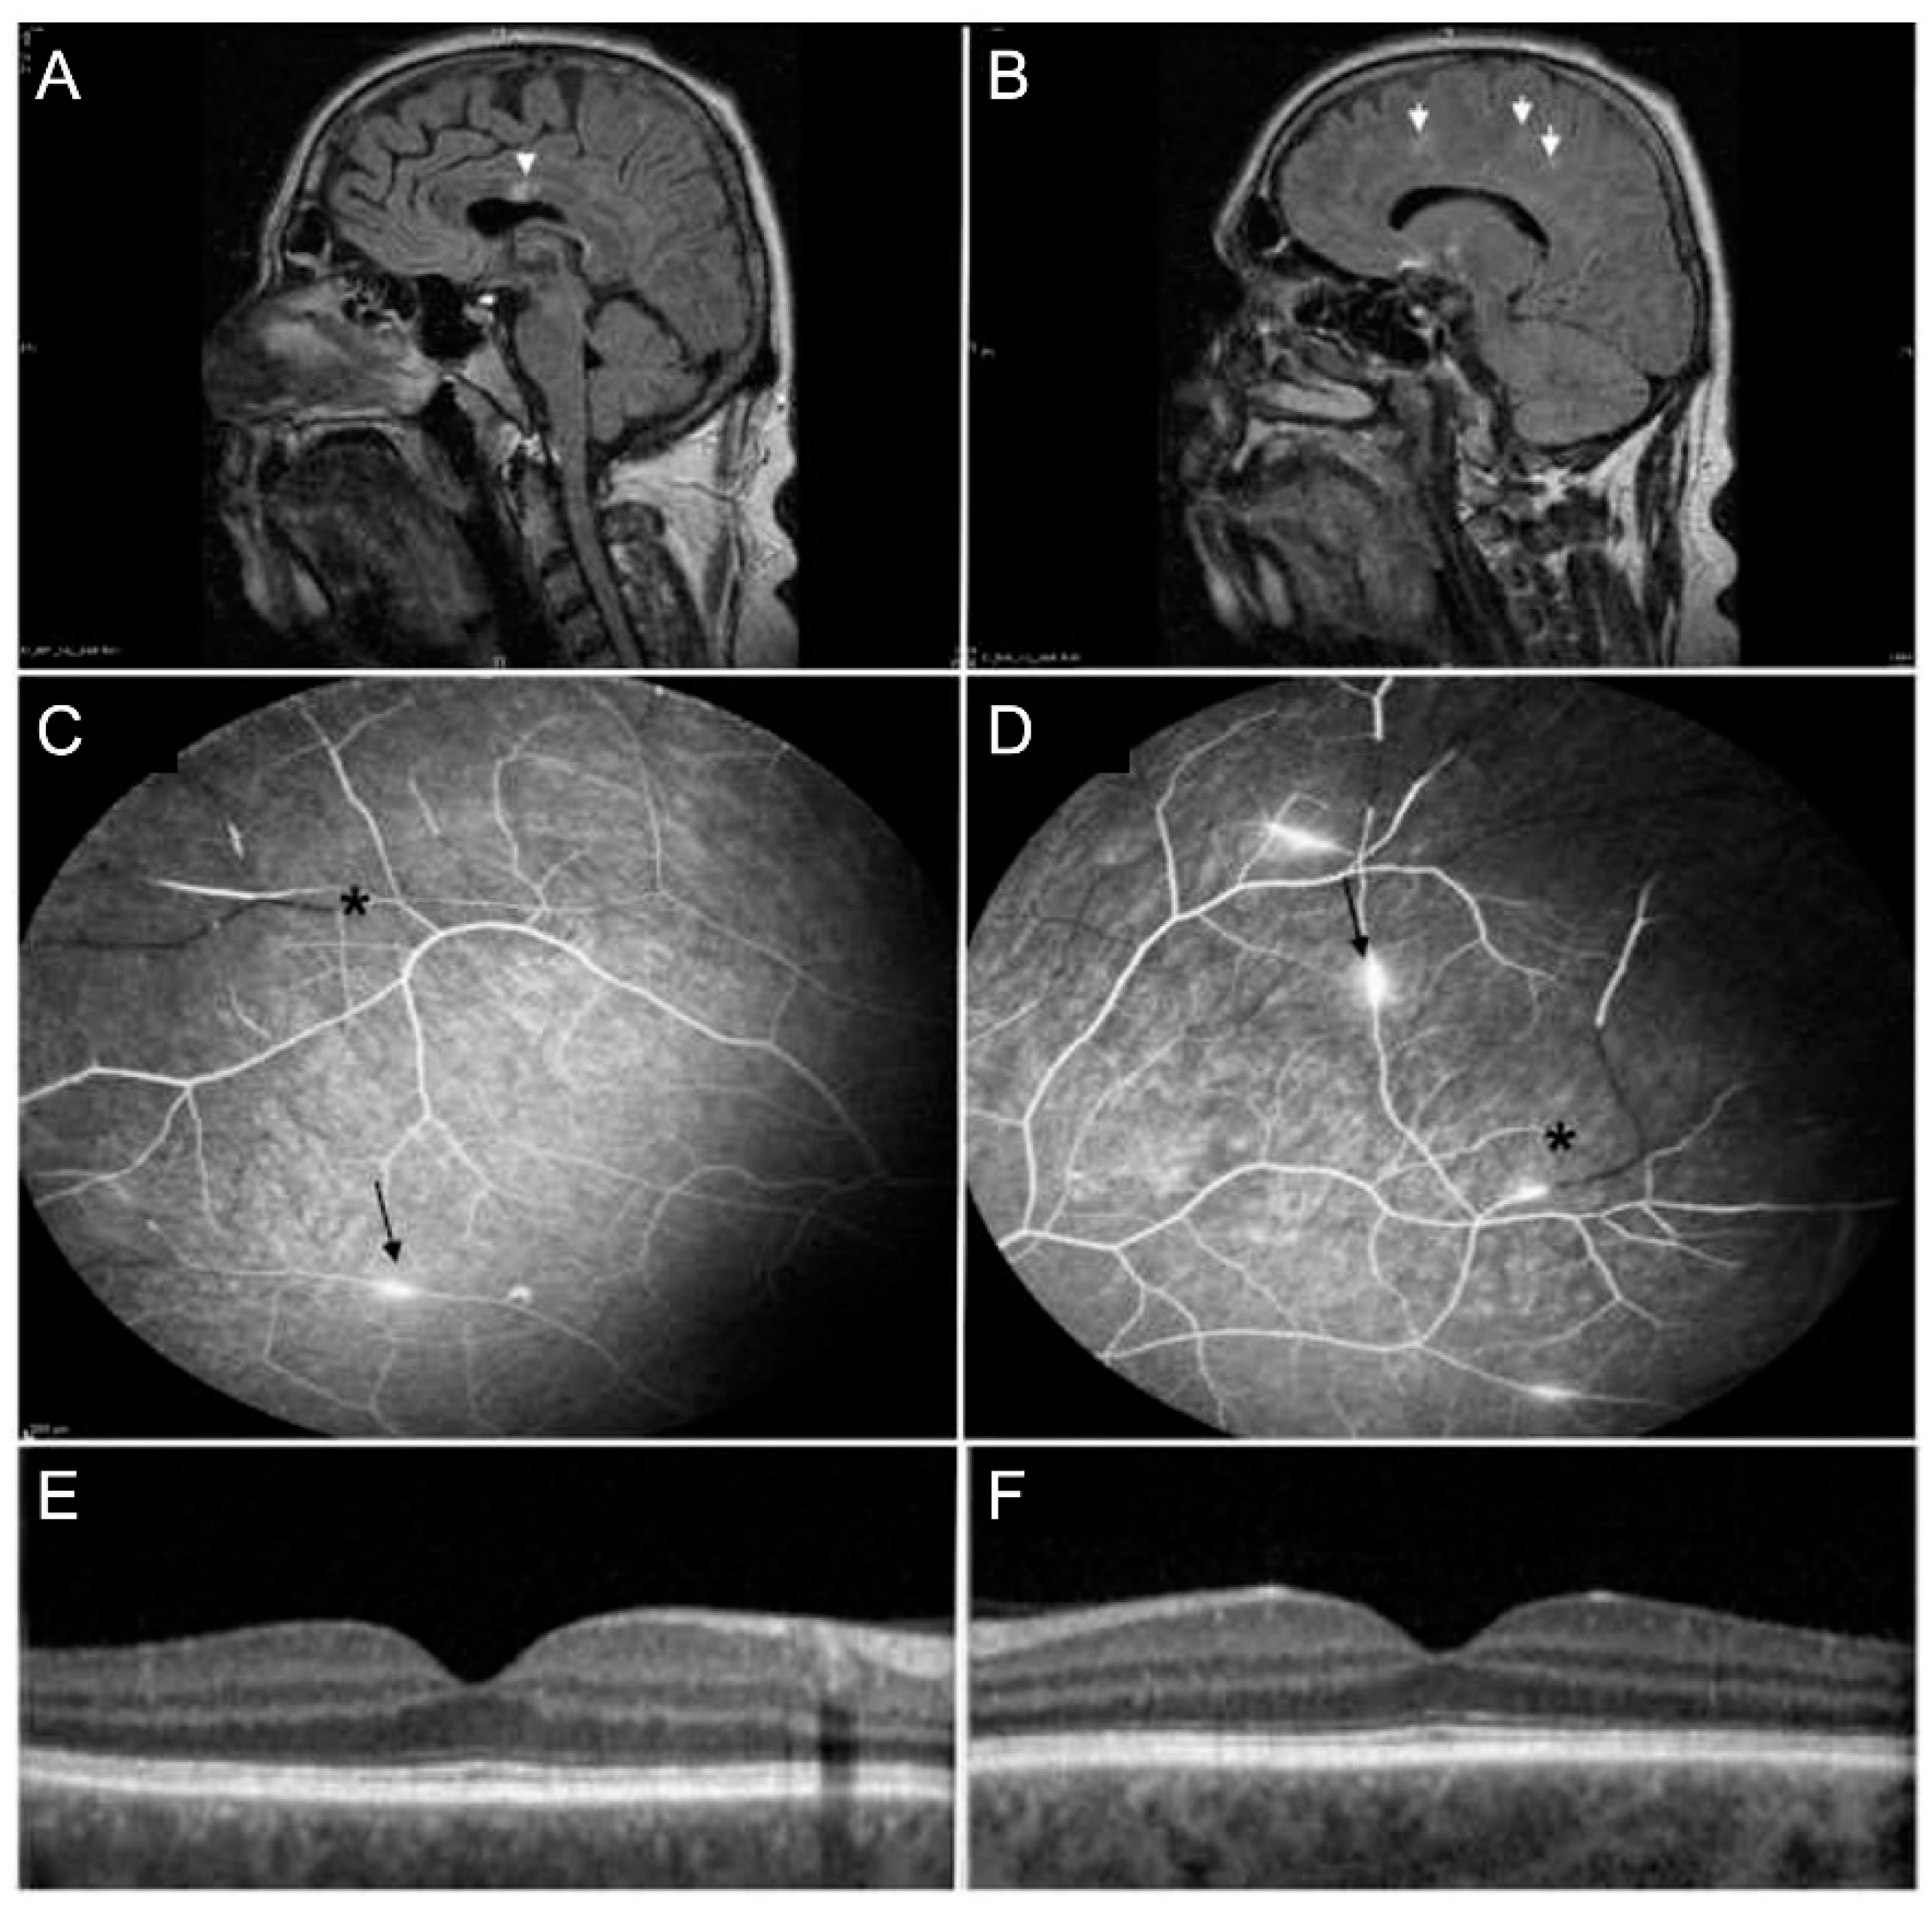

- Susac, J.O. Susac’s syndrome: The triad of microangiopathy of the brain and retina with hearing loss in young women. Neurology 1994, 44, 591–593. [Google Scholar] [CrossRef] [PubMed]

- Dörr, J.; Ringelstein, M.; Duning, T.; Kleffner, I. Update on Susac syndrome: New insights in brain and retinal imaging and treatment options. J. Alzheimers Dis. 2014, 42 (Suppl. S3), S99–S108. [Google Scholar] [CrossRef] [PubMed]

- Dörr, J.; Krautwald, S.; Wildemann, B.; Jarius, S.; Ringelstein, M.; Duning, T.; Aktas, O.; Ringelstein, E.B.; Paul, F.; Kleffner, I. Characteristics of Susac syndrome: A review of all reported cases. Nat. Rev. Neurol. 2013, 9, 307–316. [Google Scholar] [CrossRef] [PubMed]

- Egan, R.A.; Hills, W.L.; Susac, J.O. Gass plaques and fluorescein leakage in Susac Syndrome. J. Neurol. Sci. 2010, 299, 97–100. [Google Scholar] [CrossRef]

- Bagaglia, S.A.; Passani, F.; Oliverio, G.W.; Inferrera, L.; Menna, F.; Meduri, A.; Mazzotta, C. Multimodal Imaging in Susac Syndrome: A Case Report and Literature Review. Int. J. Environ. Res. Public Health 2021, 18, 3435. [Google Scholar] [CrossRef]